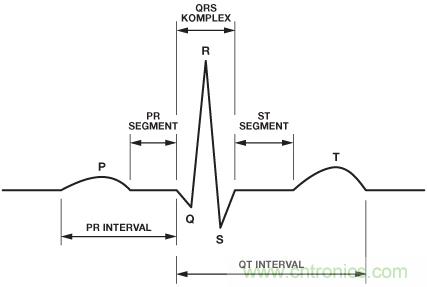

該電脈沖產(chǎn)生P波,在圖2中的ECG截圖中可以看見。電信號從房室結(jié)節(jié)開始傳播,經(jīng)過浦肯野纖維系統(tǒng),來到心室,導(dǎo)致心室肌肉收縮。這種收縮(R波)使含氧血從左心室進(jìn)入并流過身體,同時(shí)使缺氧血從右心室進(jìn)入肺部。

圖2. 心肌收縮期間電行為的ECG圖形表示2